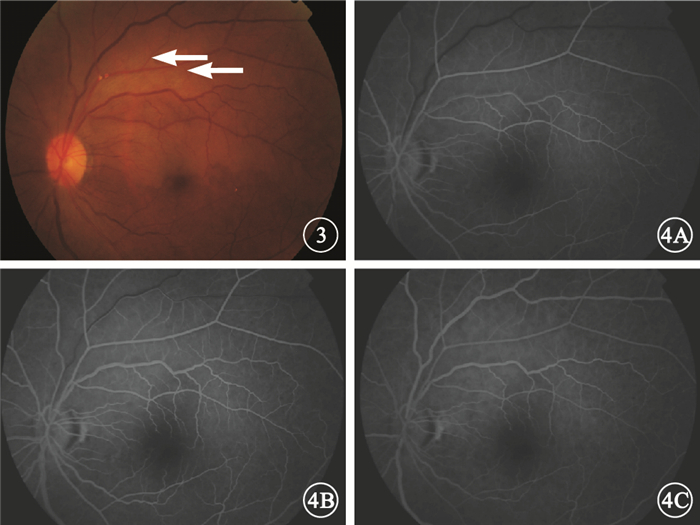

左眼治療5 d后彩色眼底像。視網膜顳上支動脈及靜脈管徑較前增粗,顳上支動脈主干分叉處的2個節段狀黃白色反光灶變小,其遠端小分支動脈閉塞區可見部分小分支動脈(白箭) 圖 4 左眼治療5 d后FFA像。4A.24.3 s,視網膜靜脈充盈,顳上支靜脈顳支仍無灌注;4B.27.9 s,顳上支靜脈顳支開始充盈;4C.38.9 s,顳上支靜脈顳支充盈完全

左眼治療5 d后彩色眼底像。視網膜顳上支動脈及靜脈管徑較前增粗,顳上支動脈主干分叉處的2個節段狀黃白色反光灶變小,其遠端小分支動脈閉塞區可見部分小分支動脈(白箭) 圖 4 左眼治療5 d后FFA像。4A.24.3 s,視網膜靜脈充盈,顳上支靜脈顳支仍無灌注;4B.27.9 s,顳上支靜脈顳支開始充盈;4C.38.9 s,顳上支靜脈顳支充盈完全

左眼治療5 d后彩色眼底像。視網膜顳上支動脈及靜脈管徑較前增粗,顳上支動脈主干分叉處的2個節段狀黃白色反光灶變小,其遠端小分支動脈閉塞區可見部分小分支動脈(白箭) 圖 4 左眼治療5 d后FFA像。4A.24.3 s,視網膜靜脈充盈,顳上支靜脈顳支仍無灌注;4B.27.9 s,顳上支靜脈顳支開始充盈;4C.38.9 s,顳上支靜脈顳支充盈完全

左眼治療5 d后彩色眼底像。視網膜顳上支動脈及靜脈管徑較前增粗,顳上支動脈主干分叉處的2個節段狀黃白色反光灶變小,其遠端小分支動脈閉塞區可見部分小分支動脈(白箭) 圖 4 左眼治療5 d后FFA像。4A.24.3 s,視網膜靜脈充盈,顳上支靜脈顳支仍無灌注;4B.27.9 s,顳上支靜脈顳支開始充盈;4C.38.9 s,顳上支靜脈顳支充盈完全